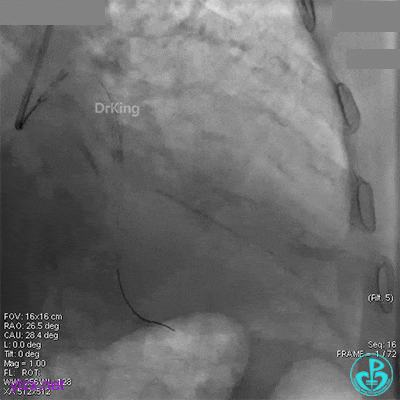

回旋支中段植入2.75×33mm支架后造影,前向血流中断,患者开始出现胸痛。

闭塞段植入2.75×33mm支架后前向血流中断,要排除无复流和支架两端夹层。

近端串联植入3.5×23mm支架后造影,前向血流没有恢复,患者感胸痛明显。

经刺破球囊冠脉内推注硝普钠后血流恢复2级,远端分支血管没有充分显影。

退出分支导丝后造影,血流不足3级。